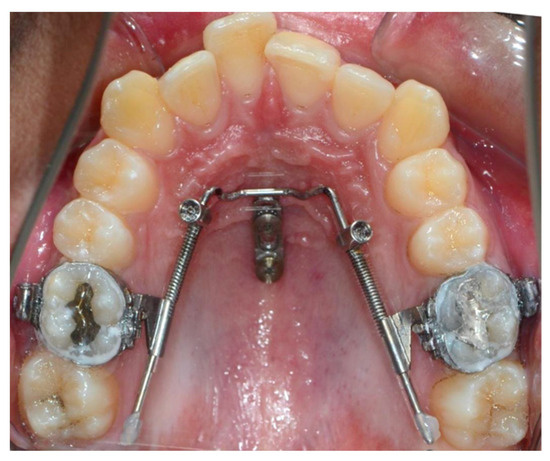

Orthodontic TAD mini-screw inserted in the gum for skeletal anchorage

TAD mini-screws for anterior open bites with braces

The front teeth do not touch when closing. The traditional approach often requires surgery. TADs allow molar intrusion to close the open bite without surgery.